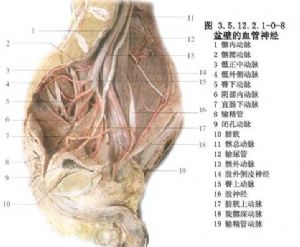

骨盆環分前後兩部分:後部是承重主弓,直立位時重力線經骶髂關節至兩側髖關節爲骶股弓(圖3.5.12.2.1-0-1);坐位時重力線經骶髂關節至兩側坐骨結節爲骶坐弓(圖3.5.12.2.1-0-2~3.5.12.2.1-0-7)。骨盆內血管十分豐富,盆壁動靜脈支緊貼盆壁而行並相互吻合成環。盆腔臟器有伴其動脈的靜脈支和異常豐富的靜脈叢(圖3.5.12.2.1-0-8,3.5.12.2.1-0-9)。後者又多圍繞盆腔內壁,且相互通連。骨盆骨折時易使鄰近的血管損傷而引起大出血,除形成盆腔血腫外,出血量大者還將沿腹膜後間隙向上擴展,形成巨大的腹膜後血腫,引起腹膜刺激症狀。此外,骨盆主要由松質骨構成,血液供應很豐富,骨折斷面可大量滲血,骨盆後壁骨折和骨盆的多發骨折尤易併發大量出血。

骨盆骨折多爲強大的外力所致。嚴重者常併發失血性休克、腹膜後血腫、盆腔或腹腔臟器撕裂傷等合併傷。因此,處理這類傷勢複雜和有生命威脅的損傷,其原則是優先搶救危及生命的合併傷,如有明顯的臟器損傷或大的血管出血,則剖腹探查。打開後腹膜間隙是禁忌的。控制出血最好的方法是儘早將骨折復位和用骨外固定維持骨折的整復,這有利於控制出血,減輕疼痛和促進全身情況的穩定。即便在需要施行剖腹探查的病人,用外固定器先將骨盆骨折固定,亦便於搬抬病人和抗治休克。

2.優先處理合並的內出血及盆腔臟器損傷,必要時進行血管造影和選擇性栓塞損傷的血管,早期固定骨盆和其他骨骼的損傷。